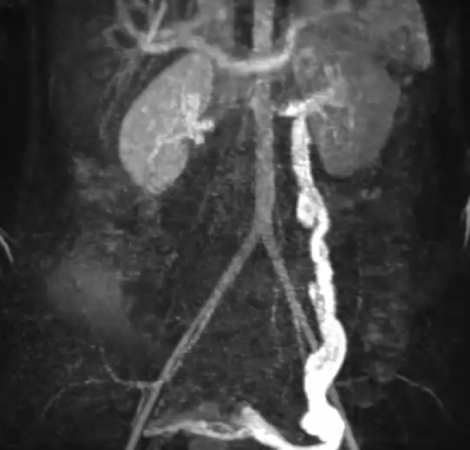

Το σύνδρομο πυελικής συμφόρησης προκαλείται από την ανεπαρκή επαναφορά του φλεβικού συστήματος, αποτελώντας συνέπεια της φλεβικής στασιμότητας. Εξαιτίας της έλλειψης ροής του αίματος στις φλέβες της περιοχής του πελβικού ιστού, όπως στα γεννητικά όργανα, την ουροδόχο κύστη και το έντερο, το αίμα αντιμετωπίζει δυσκολία στην επαναφορά του, προκαλώντας πιθανώς την εμφάνιση κιρσών στα γεννητικά όργα και τα κάτω άκρα.

Στη θεραπεία του Συνδρόμου Πυελικής Συμφόρησης, όπως και στη διαγνωστική διερεύνηση, συμμετέχουν γυναικολόγος, αγγειοχειρουργός και επεμβατικός ακτινολόγος. Αφού έχουν διερευνηθεί και αντιμετωπιστεί ή αποκλειστεί άλλες παθήσεις που μπορεί να προκαλέσουν χρόνιο πυελικό πόνο και υπάρχουν ευρήματα από τις απεικονιστικές μεθόδους συμβατά με το Σύνδρομο Πυελικής Συμφόρησης, τότε προχωρούμε στον προγραμματισμό της εξατομικευμένης αντιμετώπισης για κάθε περίπτωση, η οποία μπορεί να είναι: